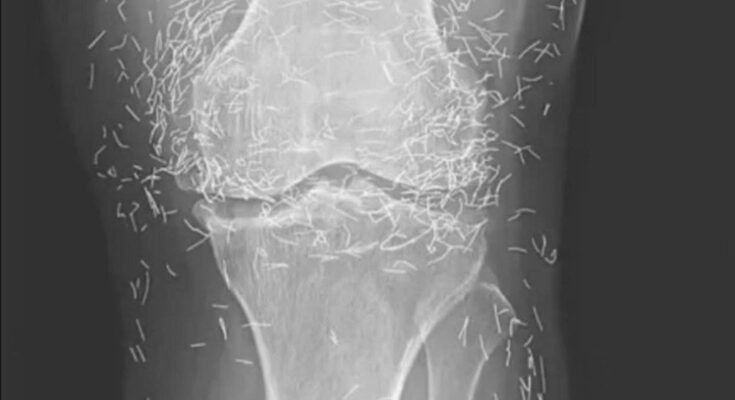

Acupuncture, an alternative treatment with a history spanning centuries, entails the insertion of needles into specific points on the body to alleviate pain or address various health issues. In this particular instance, the needles—likely crafted from gold—were deliberately left in her knees to provide ongoing stimulation.

He further cautioned that needles left embedded can interfere with X-ray interpretations. “The needles may obscure certain anatomical structures,” Guermazi remarked in 2013.

Even more troubling, needles that remain in the body can pose risks for future medical imaging. “The patient cannot undergo an MRI because needles left in the body might shift and injure an artery,” Guermazi noted.